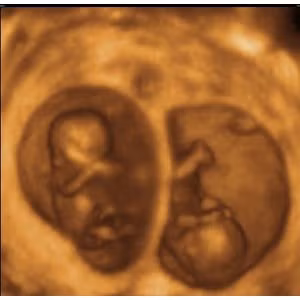

Hình ảnh chật chội của những cặp sinh đôi trong bụng mẹ

(Kiến Thức) - Những cặp sinh đôi trong bụng mẹ mặc dù có cân nặng nhỏ hơn những em bé bình thường nhưng chắc hẳn các bé vẫn cảm thấy... chật chội.

Rõ ràng một điều là những cặp sinh đôi trong bụng mẹ phải chịu cảnh chật chội hơn nhiều khi phải chia sẻ "tổ ấm" của mình cho người anh em song sinh còn lại.

Trung bình, cân nặng của bé song sinh sau khi ra đời chỉ khoảng 2,2 kg mỗi bé, với những trường hợp sinh ba, sinh tư thì cân nặng còn thấp hơn.

Trong khoảng 20 tuần đầu, các bé vẫn còn một khoảng trống rộng lớn để tha hồ "vùng vẫy" trong bụng mẹ.

Nhưng từ tuần thứ 28, khoảng không gian này bắt đầu trở nên chật chội do bọc ối và tử cung của người mẹ không thể to hơn được nữa.

Các bé sinh đôi thường có tư thế nằm trong bụng mẹ không giống nhau. Quá trình quay đầu để chuẩn bị "chui ra" có thể diễn ra ở một hoặc hai bé hoặc thậm chí không diễn ra.